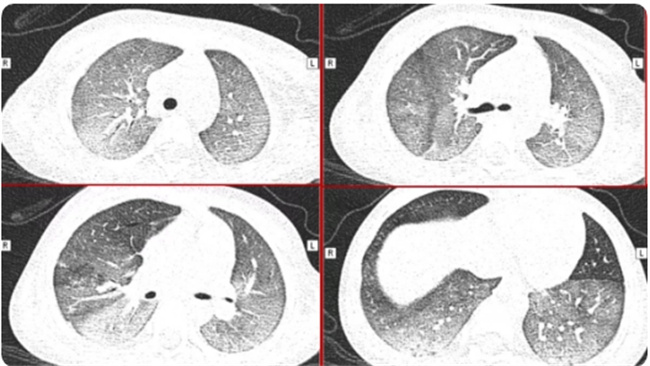

被称之为急性呼吸窘迫性综合症,一般都是在CT检查之下所形成的一种表现,可以看到有一大片的白色状。患者还会有着许多的临床症状,首先白肺患者的血氧饱和度比较低,会有呼吸不畅,会有胸闷气短等现象,而且还可能会有严重的缺氧情况。

造成白肺的原因主要是肺部原本就有感染,或者是其他部位有感染可能就会导致人体有炎症反应。炎症反应是人体生理防御机制的一种常见表现,但免疫细胞不仅仅会杀死病毒,对于自身脏器也会产生一定的创伤,因此就会形成一种白肺现象。根据观察,新冠病毒不仅仅可能就会入侵人体的上呼吸道,有时候对于人体下呼吸道也会产生影响,此时就可能会形成白肺。尤其是有糖尿病,肥胖症,结构性肺病还有阻塞性肺炎的人群受到的影响就会非常的大。